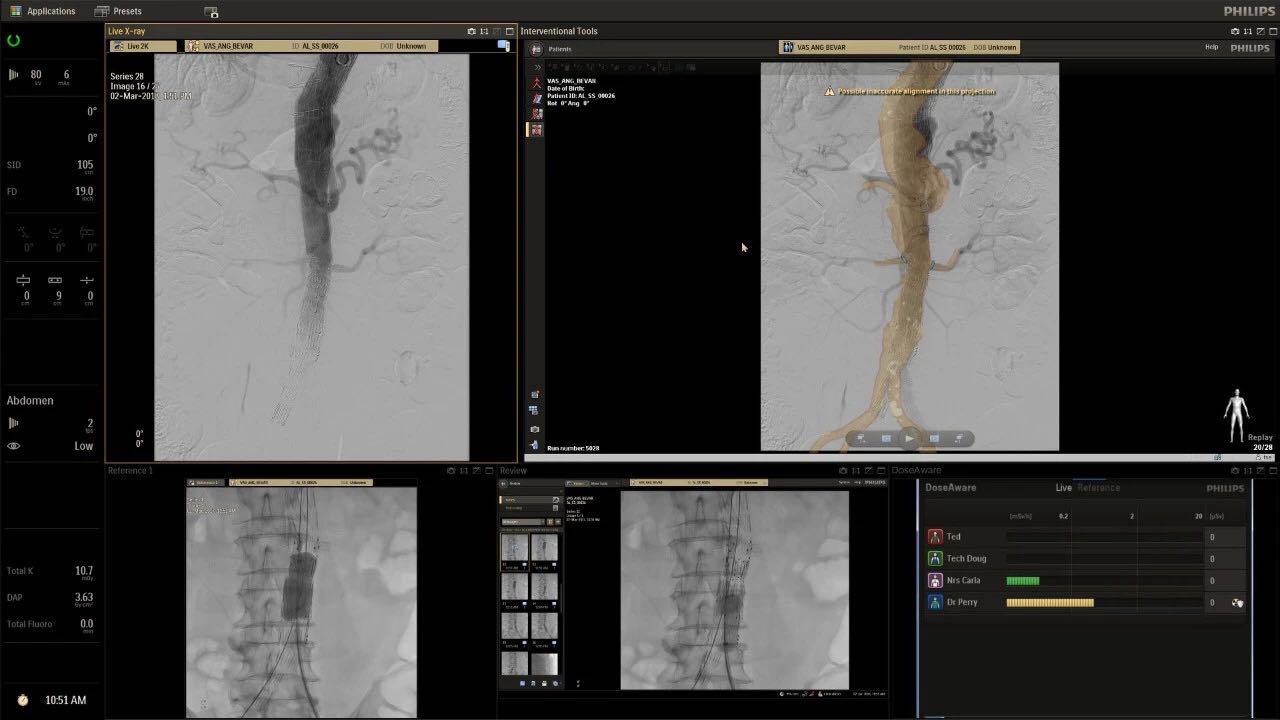

在日益復(fù)雜的干預(yù)期間,臨床醫(yī)生需要快速、輕松地可視化關(guān)鍵解剖結(jié)構(gòu)并確定手術(shù)過(guò)程中患者的變化。2019年1月17日,飛利浦宣布推出采用FlexArm的Azurion 7 C20,旨在提高圖像引導(dǎo)程序的定位靈活性。

帶有FlexArm的Azurion 7 C20 包含一系列創(chuàng)新技術(shù),使臨床醫(yī)生可以更輕松地在整個(gè)患者身上進(jìn)行二維和三維成像。當(dāng)臨床醫(yī)生移動(dòng)系統(tǒng)時(shí),圖像光束自動(dòng)保持與患者的對(duì)準(zhǔn),允許更一致的可視化并使他們能夠?qū)⒆⒁饬性谥委熒稀?/span>

(FlexArm C型臂可以沿著工作臺(tái)的兩側(cè)提供偏心成像。這允許醫(yī)生在左臂或右臂上進(jìn)行徑向進(jìn)入病例,完全或部分伸展,而無(wú)需移動(dòng)患者或樞轉(zhuǎn)桌子。X射線束與手臂保持對(duì)齊,以促進(jìn)其整個(gè)長(zhǎng)度的平滑導(dǎo)航,而無(wú)需進(jìn)行持續(xù)調(diào)整。)

飛利浦表示,采用FlexArm設(shè)計(jì)的Azurion 7 C20可提供卓越的靈活性和直觀的控制。該系統(tǒng)由智能運(yùn)動(dòng)引擎驅(qū)動(dòng),可在八個(gè)不同的軸上移動(dòng),所有這些軸均由其單個(gè)“Axsys”控制器控制。臨床醫(yī)生的模擬測(cè)試表明,該系統(tǒng)有可能顯著減少患者,工作人員和設(shè)備的重新定位,從而改善微創(chuàng)手術(shù)的可及性,包括通過(guò)患者手腕進(jìn)入身體的手術(shù)(橈動(dòng)脈入路),并降低患者的風(fēng)險(xiǎn)。無(wú)意中拔出電線和管子,以及節(jié)省大量時(shí)間。該系統(tǒng)非常適合混合手術(shù)室(OR),可滿足一個(gè)房間內(nèi)的多種專業(yè)需求,例如手術(shù)和血管內(nèi)手術(shù)的組合。

FlexArm在不少于8軸的情況下旋轉(zhuǎn),從而創(chuàng)建幾乎無(wú)限的靈活性來(lái)執(zhí)行成像,從頭部到腳部在左側(cè)和右側(cè)進(jìn)行2D和3D可視化。圖像光束保持與患者對(duì)齊,允許在旋轉(zhuǎn)或角度期間更好地可視化解剖結(jié)構(gòu)。使用Axsys運(yùn)動(dòng)控制系統(tǒng)輕松操作支架。